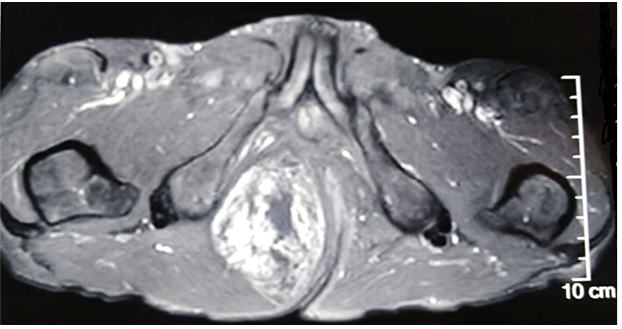

A 69-year-old male patient, consulted with complaints of swelling in the right gluteal region gradually increasing in size for 3 years, with no other associated signs. The clinical examination objected a freely mobile large mass of the right gluteal region measuring 7cmx10cm, soft, non-painful and with no inflammatory signs. There was no history of previous trauma. Magnetic resonance imaging (MRI) revealed a large, well defined mass of the right ischio-rectal pit. It showed high signal on a T2-weighted image (Figure 1), heterogeneous, iso-signal on a T1-weighted image (Figure 2), and a gadolinium-enhanced image (Figure 3), measuring 76-49-108 mm coming into contact with the internal shutter muscle outside, pushing back the anal canal into it without signs of invasion. On the basis of these radiological findings, we suspected a desmoide tumor, or liposarcoma from which the surgical indication was put. The patient was operated on with a single-block excision of the mass without capsular break-in (Figure 4-6). The surgical suites were simple. A histopathological examination revealed a well circumscribed mass composed of a mixture of mature adipocytes and spindle cells in varying proportions surrounded by a clear fibrous capsule. Neither the lipomatous nor the spindle cell elements of the tumors showed evidence of necrosis or mitotic activity. The immune histochemical analysis, showed that the lesional spindle cells were strongly immunoreactive for CD34 and the results of MDM2 immunostaining were negative. The diagnosis of SCL of the gluteal region was concluded.

Figure 2 Axial section of Pelvic MRI revealing heterogeneous mass with iso-signal on a T1-weighted image.